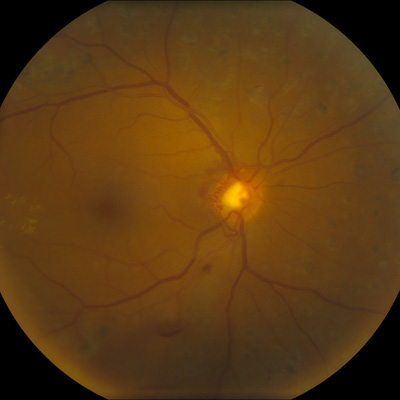

Cataract surgery in a patient with diabetes requires special considerations, careful examination, and it may be helpful to have a retina specialist involved.